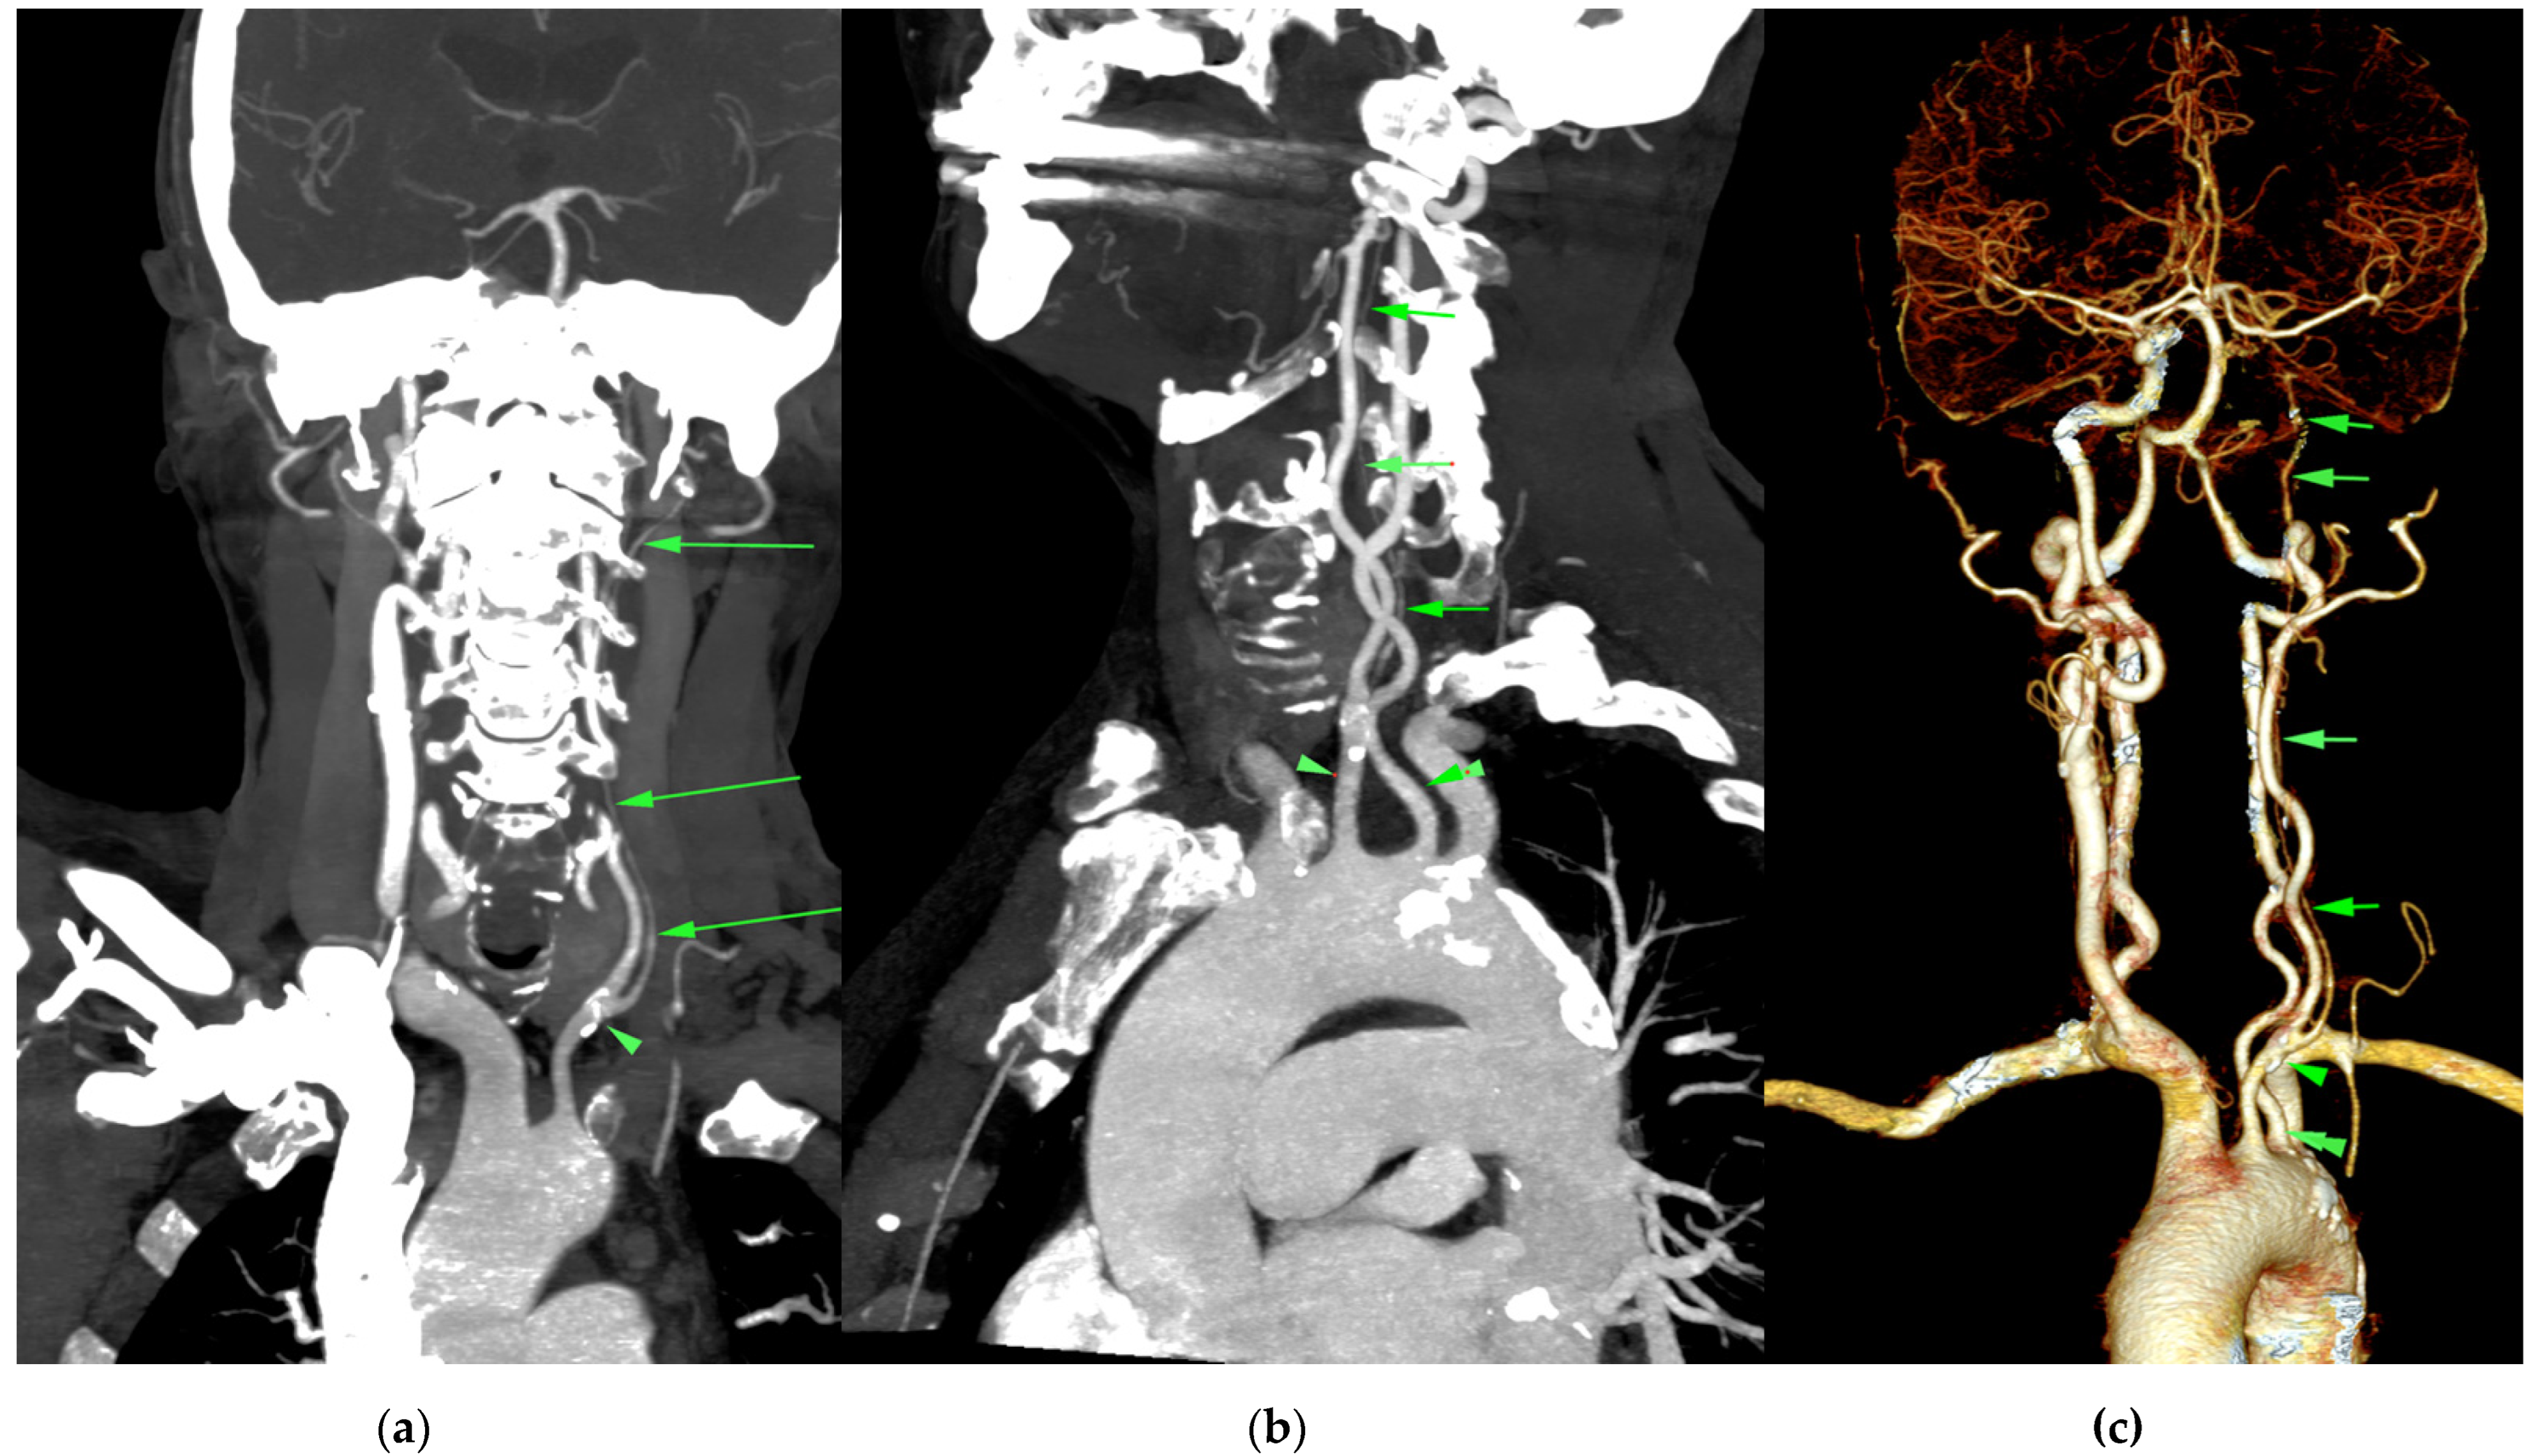

2. Case Report